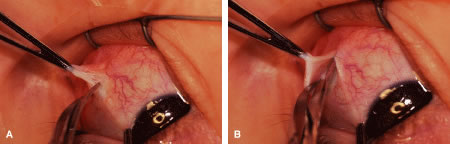

A Stevens' hook is inserted in the opening in the intermuscular septum created by the scissors and is passed anterior to the insertion. Parks has referred to this maneuver as the “pole test.” This maneuver is done to verify that the tendon of the muscle has not been split and that the complete muscle tendon is incorporated on the hook. Leaving residual slips of muscle tendon will partially or completely negate the effect of a recession procedure (Fig. 20A and B).